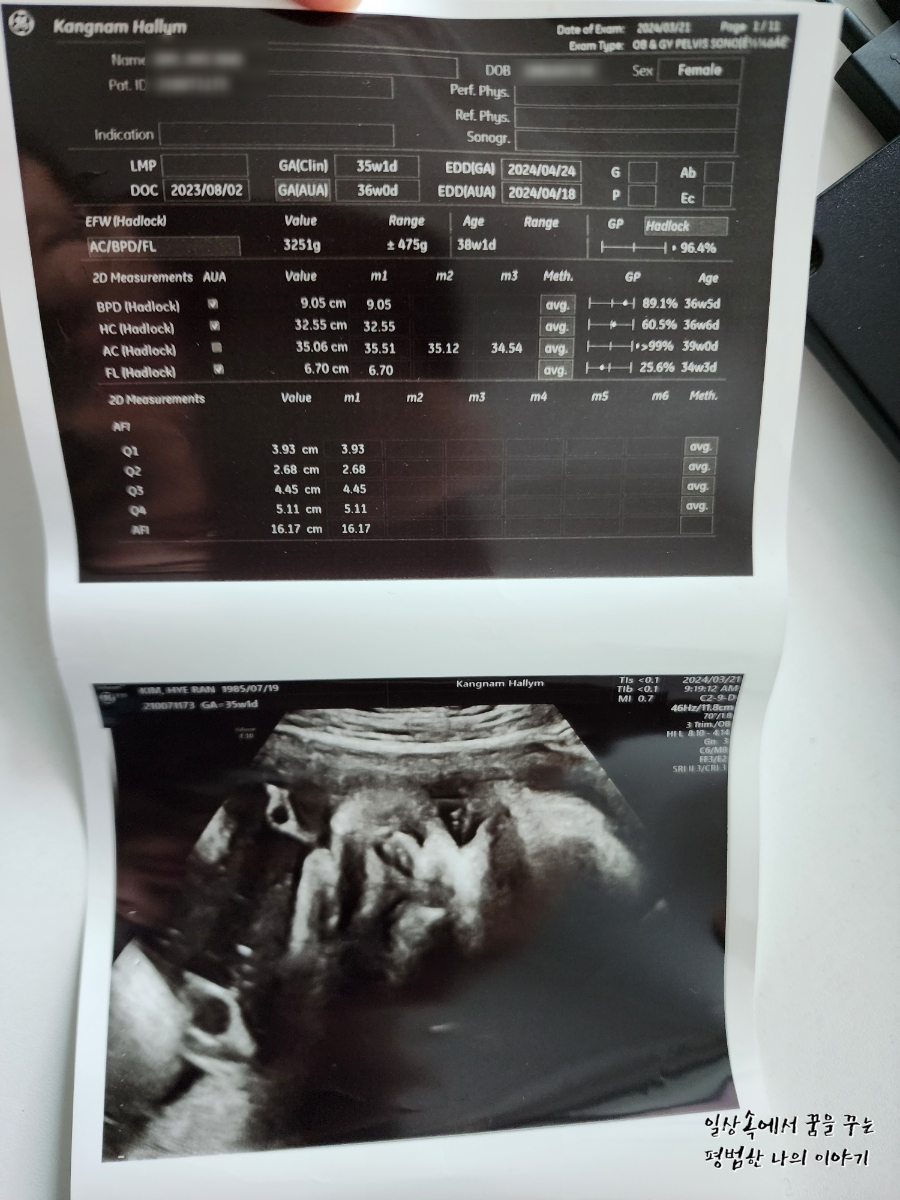

3주 만에 방문한 병원에서 딸내미는 더욱 커져서 35주 차에 첫째 37주 차 때 사이즈와 모든 게 비슷해져 있었다.(머리둘레, 배 둘레, 몸무게 등) 첫째를 꽉 채운 40주 차에 유도 분만으로 출산했는데 4.09kg으로 무척 커서 출산하고 의료진과 함께 놀랐던 기억이 있다. 둘째는 이를 훨씬 앞서고 있으니 의사 선생님도 40주까지 기다리는 건 무리가 있다고 생각하시는 것 같다. 나는 38주 차에 유도 분만을 하고 싶으나 의사 선생님은 39주까지 채우고 유도 분만 하기를 권하셨다. 우선 나의 몸이 아무런 준비가 되지 않았기 때문에 유도 분만이 실패할 가능성이 있어 38주보다는 39주 차를 더 선호하시는 것 같다. 나는 첫째가 4.09kg으로 태어난 탓에 우량아라 인큐베이터에 일주일이나 있었던 게 싫었던지라 이번에는 어떻게든 4kg 미만으로 아이를 출산하여 나와 함께 퇴원하고 싶은 마음이 크다. 그러면서도 최대한 유도 분만을 하고 싶고 제왕절개로 상황이 흘러가게 되는 건 또 싫어 고민이 많다. 여태까지 나의 몸무게는 9kg 정도 늘었는데 첫째 때보다는 양호한 수준이다. 그래도 또 알 수가 없는 게 막달에 일주일에 1~2kg은 쉽게 몸무게가 늘기 때문에 첫째 때만큼 살이 찐 상태에서 출산할 가능성도 없지 않다.